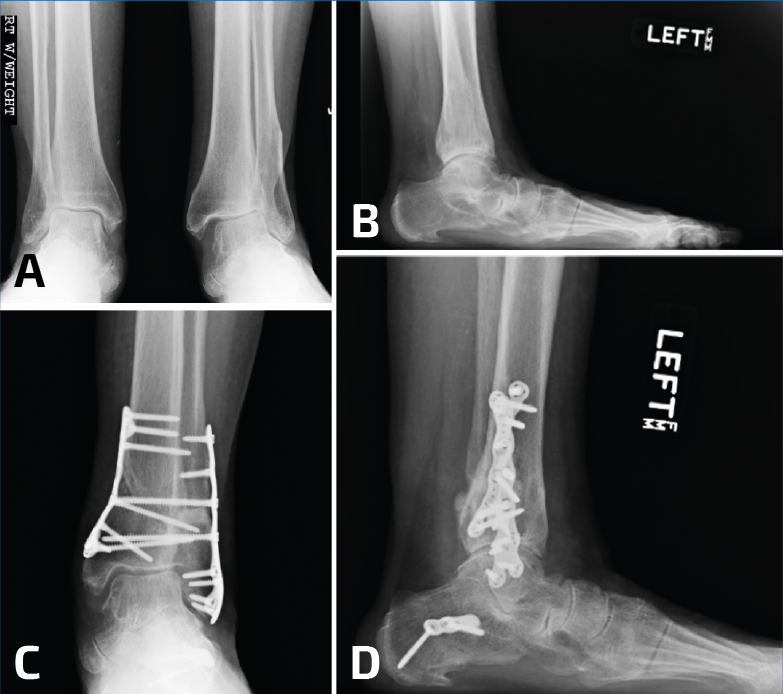

Se puede recurrir a la osteotomía de la tibia para corregir la deformidad en valgo del pilón. Esto se puede realizar mediante una cuña de sustracción interna o una cuña de adición externa de la tibia (Figura 6). En este caso, la consolidación viciosa oblicua del peroné facilitará la osteotomía oblicua del mismo para lograr una buena elongación y en este caso no se utilizaría injerto óseo(11).

Figura 6. En un caso donde el plafón tibial se encuentra en valgo, solo elongar el peroné no será suficiente. Observen el pie plano como resultado del tobillo y el retropié en valgo (A, B). Se realizaron conjuntamente una elongación del peroné, una osteotomía en cuña de cierre con base medial de la tibia y una osteotomía medializadora del calcáneo. Observen una mejoría en la alineación, pero la persistencia de un leve valgo de tobillo (C, D).

Figura 8. Generalmente, las deformidades en valgo del plafón tibial se acompañan con deformidades severas del peroné; sin embargo, a veces pueden ser consecuencia de una fractura de Weber B (A, B). En este caso, la gotera interna se limpió por artroscopia, se elongó el peroné, pero todavía hacía falta una osteotomía de cierre de base medial (C).

Otra variante de una consolidación viciosa del peroné se asocia con la compresión del pilón externo y la inclinación en valgo de la mortaja del tobillo. Como se describió más arriba, estos casos deben tratarse mediante osteotomía del peroné, además de una osteotomía en cuña de sustracción de la cara interna de la tibia para la realineación del tobillo (Figuras 8 y 9).

Figura 9. Las consolidaciones viciosas o pseudoartrosis del peroné pueden producirse en el contexto de una fractura de estrés. En este paciente, una fractura por estrés tras una triple artrodesis indica una deformidad en valgo (A, B). A pesar de elongar 1 cm el peroné, se debe realizar una osteotomía de cierre lateral de la tibia distal (C, D).